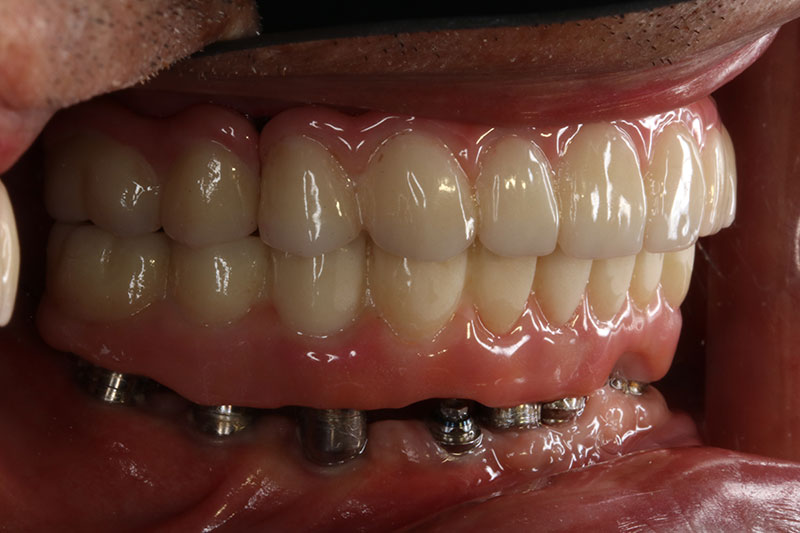

銀髮族植牙 全口植牙重建

案例一

術前

術後